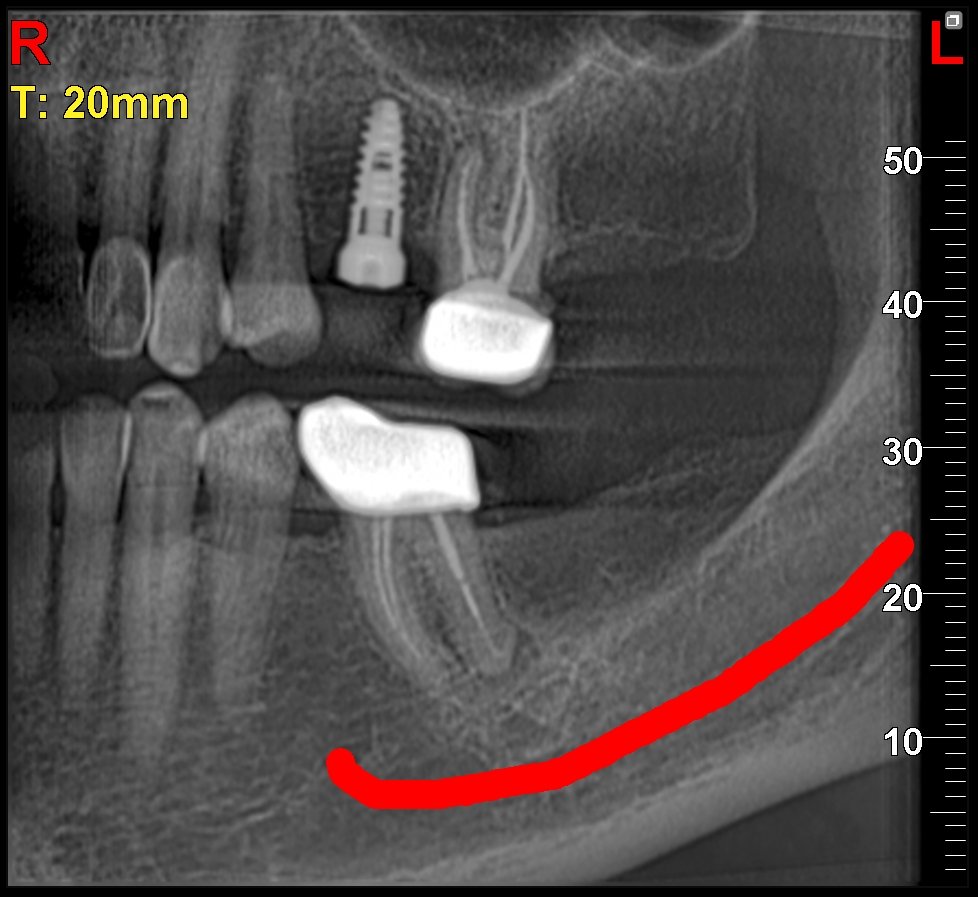

Imágenes 2D-3D Radiografías, Tomografías DENTAL, ATM, SPN, OIDO

Nuestra tecnología Cone Beam 3D permite visualizar estructuras óseas y dentales con alta definición, favoreciendo diagnósticos exactos y resultados clínicos confiables.